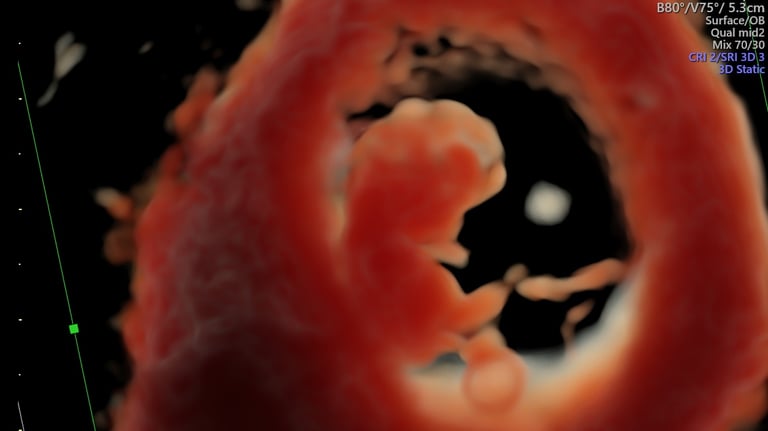

ecografía de viabilidad

4 - 11 semanas